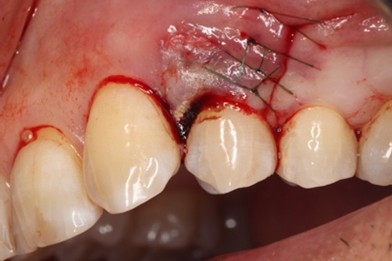

Er:YAGレーザーを併用した歯周組織再生療法の症例紹介

Before

初診時歯周ポケット6mm、左上4番に骨吸収を認める

切開はEPPT(entire papilla preservation technique)

治療中

エムドゲイン®サイトランス®を填入し、レーザーにて血餅形成、縫合

主訴

他院で歯周病と言われ紹介されました

歯周基本治療後に再評価し、ポケットが残存したのでEr:YAGレーザーを併用した歯周組織再生療法(エムドゲイン® 、サイトランス®を使用)を行ったケース

歯周病の好発部位である上顎第一小臼歯近心面における骨吸収に対して再生療法を行ったケース。一般的に根面溝という溝があり歯石の沈着が生じやすい。また溝の存在により術後に歯肉と歯根の付着が生じにくいため、今回はEr:YAGレーザーにて血餅形成を行い組織の安定化を図った。